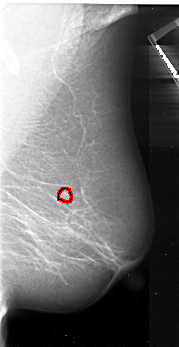

A_1048_1.LEFT_MLO

LEFT_MLO LINES 5101 PIXELS_PER_LINE 2491 BITS_PER_PIXEL 16 RESOLUTION 42 NON_OVERLAY

FILE: A_1048_1.RIGHT_MLO.OVERLAY

TOTAL_ABNORMALITIES 1

ABNORMALITY 1

LESION_TYPE MASS SHAPE IRREGULAR MARGINS ILL_DEFINED

ASSESSMENT 4

SUBTLETY 5

PATHOLOGY MALIGNANT

TOTAL_OUTLINES 1

BOUNDARY